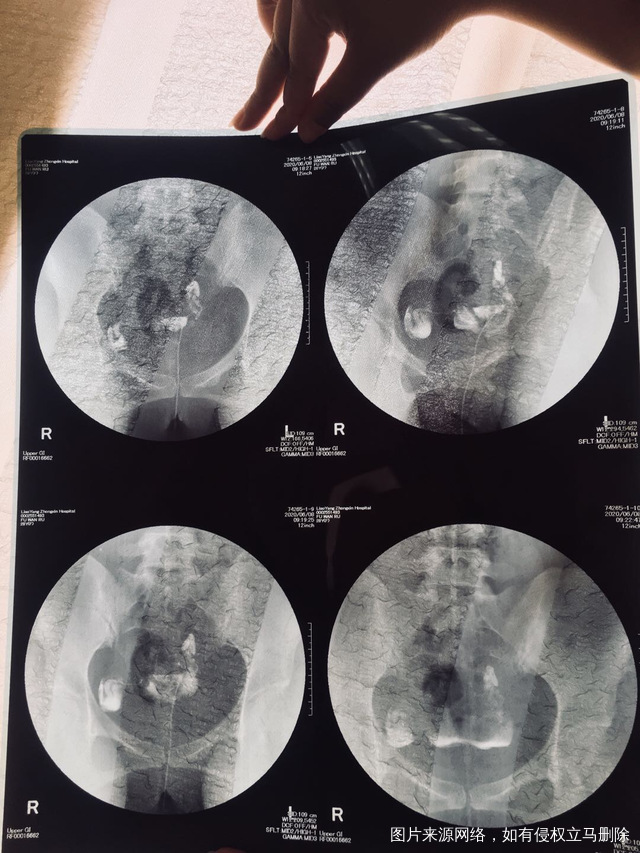

做完输卵管造影第六天了小腹还是感觉沉甸甸的如

可以热敷腹部,如果有发热,腹痛加剧,白带量多,有异味,随时就医